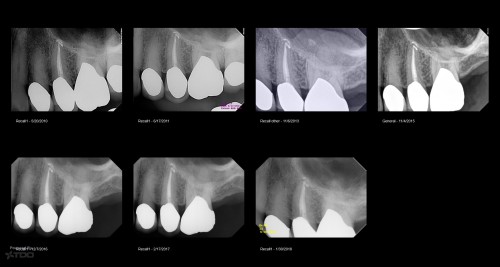

First TDO Outcomes Failure

Collage-2140634438-Page00